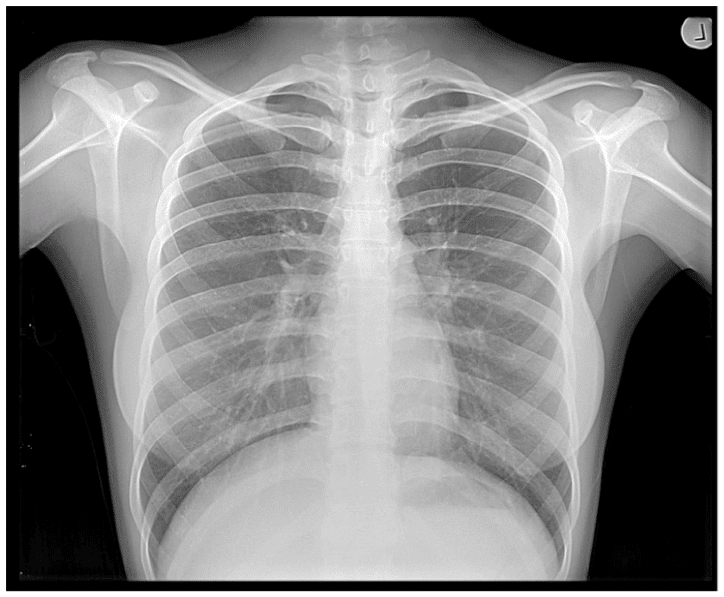

Dense parts of your body that X rays find it more difficult to pass through, such as bone, show up as clear white areas on the image. Softer parts that X-rays can pass through more easily, such as your heart and lungs, show up as darker areas. Thus we get images like this, which we’ve all seen: